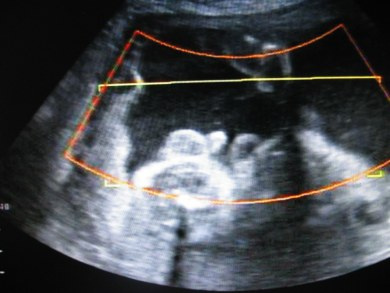

Могут ли на узи перепутать пуповину с членом - фото презентация